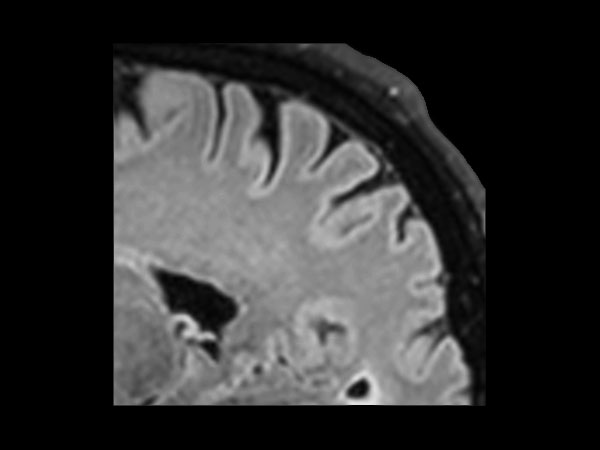

dS SENSE in Brain Imaging

Used Solution

• Clinical Application